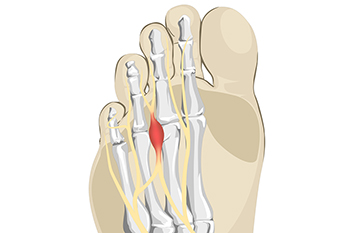

Morton neuroma is a nerve-related condition that causes burning pain, tingling, or numbness in the ball of the foot. It usually develops between the third and fourth toes when the nerve becomes irritated and thickened from repeated pressure. Wearing tight shoes, high heels, and high impact activities often worsen the problem. When shoe changes, padding, and activity modification do not bring relief, injection therapy may be considered. This treatment involves carefully placing medication around the affected nerve to reduce inflammation and calm nerve irritation. Corticosteroid injections are commonly used to decrease swelling and pressure in the surrounding tissues. Some patients also receive alcohol-based injections that help shrink the enlarged nerve over time. These treatments are performed in a clinical setting and are designed to relieve pain while improving walking comfort. When persistent forefoot pain suggests Morton neuroma, a consultation with a podiatrist is suggested to discuss diagnosis and appropriate treatment options.

Morton’s neuroma is a very uncomfortable condition to live with. If you think you have Morton’s neuroma, contact Brent Harwood, DPM of Southeast Podiatry. Our doctor will attend to all of your foot care needs and answer any of your related questions.

Morton’s Neuroma

Morton's neuroma is a painful foot condition that commonly affects the areas between the second and third or third and fourth toe, although other areas of the foot are also susceptible. Morton’s neuroma is caused by an inflamed nerve in the foot that is being squeezed and aggravated by surrounding bones.

What Increases the Chances of Having Morton’s Neuroma?

Morton’s neuroma is a very treatable condition. Orthotics and shoe inserts can often be used to alleviate the pain on the forefront of the feet. In more severe cases, corticosteroids can also be prescribed. In order to figure out the best treatment for your neuroma, it’s recommended to seek the care of a podiatrist who can diagnose your condition and provide different treatment options.